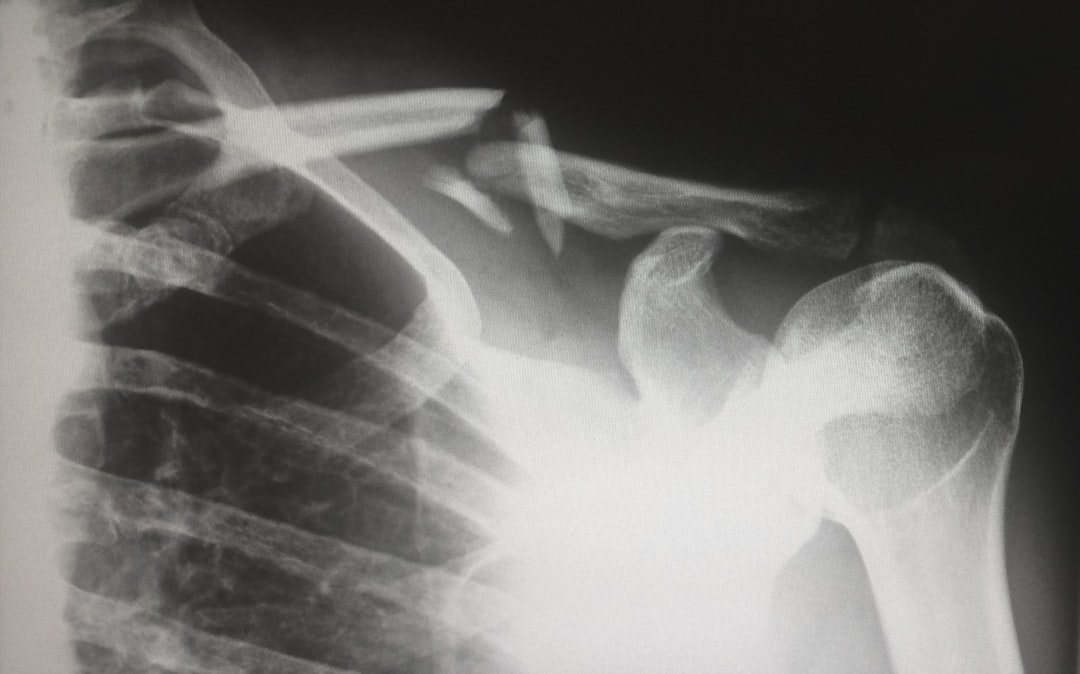

사실, 쇄골은 뼈 중에서도 상대적으로 약한 편입니다. 일상 생활에서 쉽게 부상을 입을 수 있는 부위이기도 하죠. 특히, 스포츠 활동이나 사고로 인해 부러질 경우가 많아 주의가 필요합니다. 그렇지만 참 재미있는 사실은, 쇄골이 손상되더라도, 인체는 시간이 지나면서 스스로 회복할 수 있는 능력을 가지고 있다는 점입니다.

그렇다면 쇄골의 구조와 함께하는 손상이나 염증에 대해 알아보겠습니다. 쇄골 주변은 관절, 인대 및 근육이 매우 밀접하게 얽히고 있습니다. 따라서 부상이나 염증이 발생할 경우 각 구조 요소가 어떻게 연결되어 있는지에 따라 치료 과정이 달라질 수 있습니다. 이러한 이유로 인해, 쇄골 부위의 부상은 상당히 흔합니다.

특히 스포츠 활동 중 늘어나는 힘과 충격은 쇄골을 부러트릴 위험을 증대시킵니다. 예를 들어, 자전거를 타거나 스키를 즐길 때 넘어지는 충격이 쇄골에 가해지면, 중대한 손상이 발생할 수 있습니다. 그리고 이런 상황이 발생했을 땐, 통증이 치명적인 수준으로 느껴질 수 있습니다.